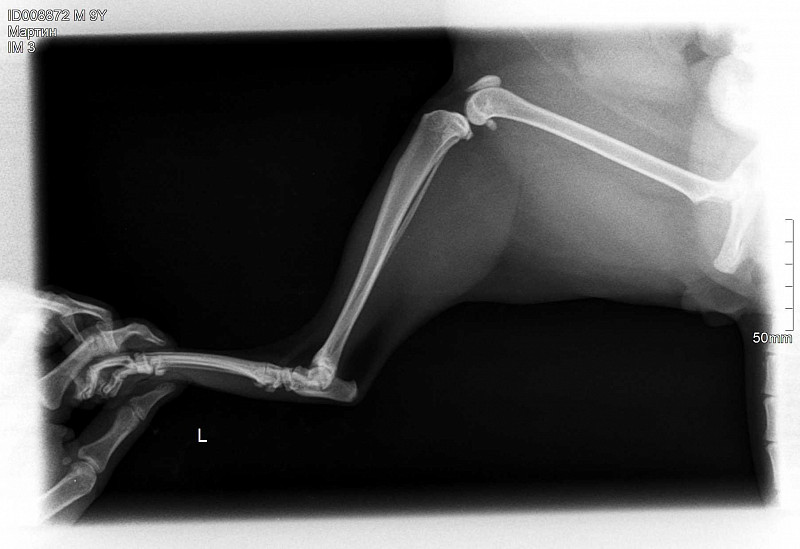

Рентген Задней Лапы Кошки: Нормы и Диагностика